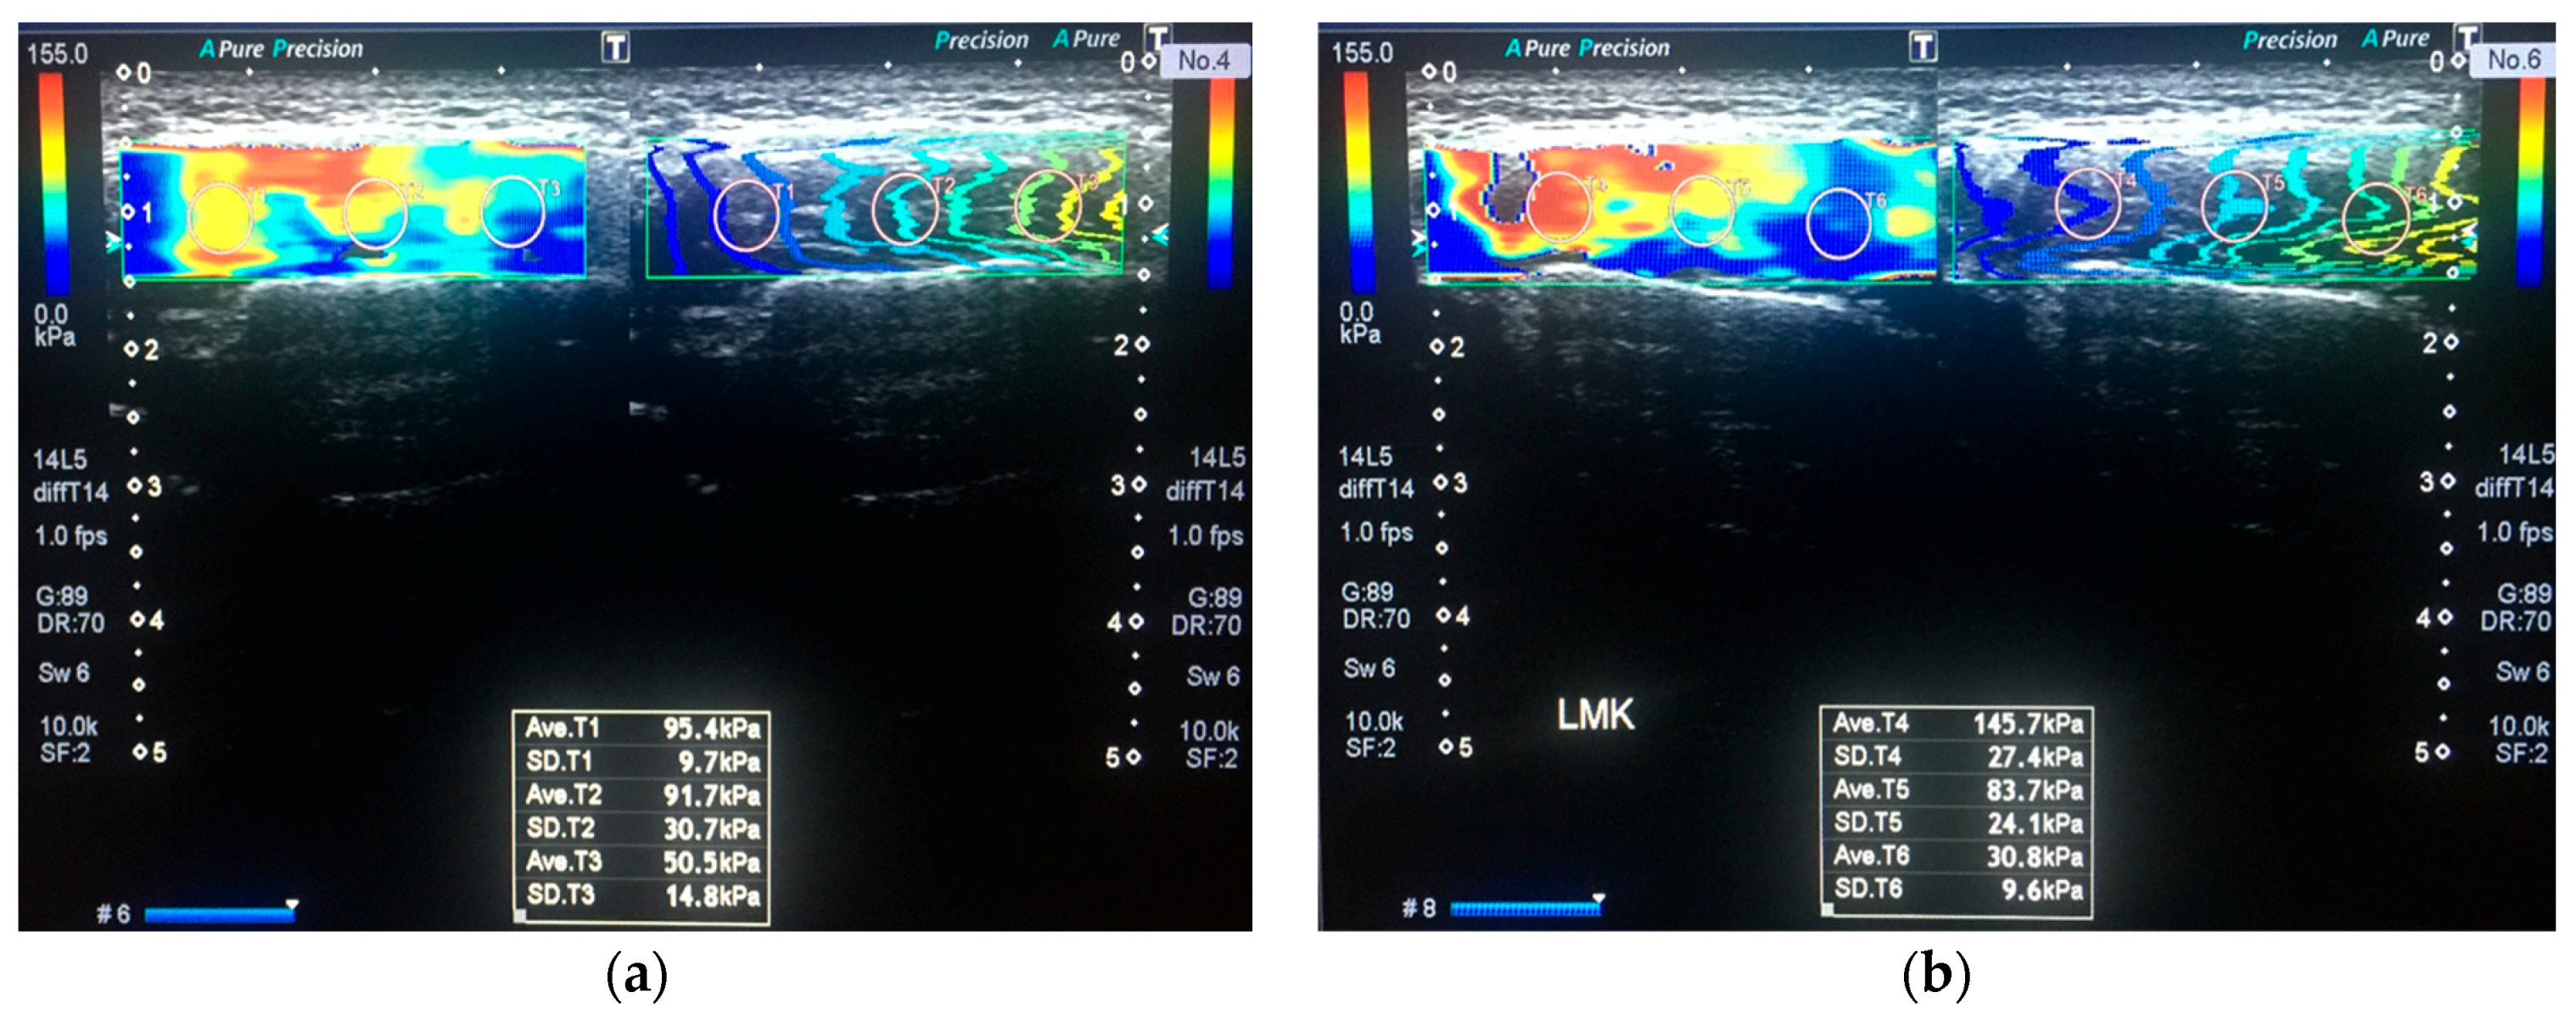

2.3. Imaging and Measurements